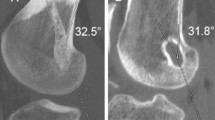

Clinical evaluations

An independent orthopedic surgeon performed all clinical evaluations at 2 years after the surgery. For the evaluation of knee stability, the anterior laxity of the normal and reconstructed knees was measured with the KT-1000 arthrometer. Differences between both knees were calculated. At least three measurements were performed on each knee, and the mean value was recorded. Passive knee range of motion was measured with a goniometer and compared with that of the contralateral knee. The pivot-shift test was performed manually and graded as 0 (negative), 1 (glide), 2 (clunk), and 3 (gross). All subjects were asked to complete self-reported knee function surveys, including the Lysholm knee score [15] and the International Knee Documentation Committee (IKDC) questionnaire [16]. To calculate bone tunnel enlargement, we compared computed tomography (CT) images taken at 1 week after the surgery with those taken at 3 months after the surgery. We identified the slice of the femoral opening using the AquarisNET (TeraRecon Inc., Foster City, CA) program, made a cross-sectional slice of 2-mm depth near the opening of the bone tunnels, and measured the femoral bone tunnel area. We traced the tunnel wall within the sclerotic bony margin and measured the tunnel area that was surrounded by trace lines (Fig. 3). Measured tunnel areas were compared within each period, and the bone tunnel enlargement ratio was calculated according to the following equation: bone tunnel enlargement ration (%) = (tunnel area 3 months after surgery – tunnel area 1 week after surgery) / tunnel area 1 week after surgery × 100.

The RFTR group had a larger femoral tunnel area than the ASBR group (average area, 53.1 ± 4.0 mm2 vs. 46.1 ± 7.0 mm2; P < 0.01). The RFTR group had better anteroposterior stability and higher Lysholm scores than the ASBR group (average side-to-side difference for anterior tibial translation, 0.6 ± 0.8 mm vs. 1.6 ± 1.4 mm; P < 0.01; average Lysholm score, 98.5 ± 2.1 vs. 97.5 ± 3.5; P < 0.01). Differences in rotational laxity between the groups were significant (negative pivot shift, 94.3% vs. 92.3%; P < 0.01). No significant difference was noted in the IKDC subjective score between the two groups. The RFTR group had significantly larger femoral bone tunnels immediately after surgery; however, no significant differences were observed in bone tunnel area on the 3-month postoperative CT (106.2 ± 23.8 mm2 vs. 102.1 ± 24.8 mm2; p = 0.264). The bone tunnel enlargement ratio was significantly lower in the RFTR group (73 ± 38% vs. 107 ± 41%; P < 0.01) (Table 2). No surgical site infections were detected in both groups. Two patients experienced partial posterior tunnel wall blowout; we were able to fix the graft using the standard technique. No other intraoperative/postoperative complications were observed.